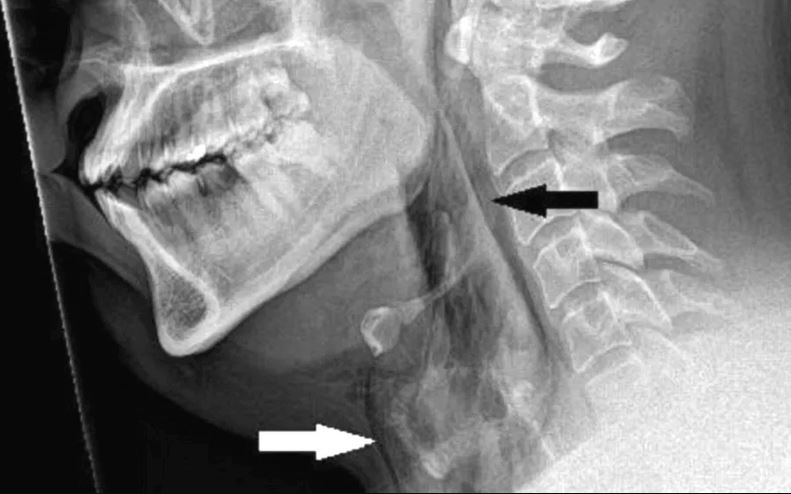

এর ফলে কানের পর্দা ফেটে যাওয়া, অ্যানিউরিজম, এমনকি বুকের পাঁজরের হাড়েও আঘাত লাগতে পারে।নাম প্রকাশে অনিচ্ছুক ওই ব্যক্তি একই সঙ্গে নাক চেপে ও মুখ বন্ধ করে হাঁচি দেওয়ার পর গলায় তীব্র ব্যথা অনুভব করেন। হাসপাতালে স্ক্যান করার পর দেখা যায়, তাঁর শ্বাসনালিতে ২ মিলিমিটারের মতো জায়গা ছিঁড়ে গেছে। ঘটনাটি মেডিক্যাল জার্নাল বিএমজে কেস প্রতিবেদনে নথিভুক্ত করা হয়েছে।

কারণ হাঁচি নাকের ভেতর থেকে বিরক্তিকর সব পদার্থ বের করে দেওয়ার প্রাকৃতিক প্রতিরক্ষামূলক ব্যবস্থা। তিনি বলেন, ‘হাঁচি দেওয়ার সময় হাত বা কনুই দিয়ে আলতোভাবে নাক ঢেকে দেওয়া উচিত।’আচমকা শ্বাসনালি ছিদ্র হয়ে যাওয়াকে ডাক্তারি ভাষায় ‘স্পন্টেনিয়াস ট্রিকি পারফোরেশন’ বলে। এটি বিরল এবং এতে মৃত্যুঝুঁকিও রয়েছে। ২০১৮ সালেও এক ব্যক্তি হাঁচি ধরে রাখার চেষ্টা করলে শ্বাসনালি ছিঁড়ে যায়। সূত্র : বিবিসি